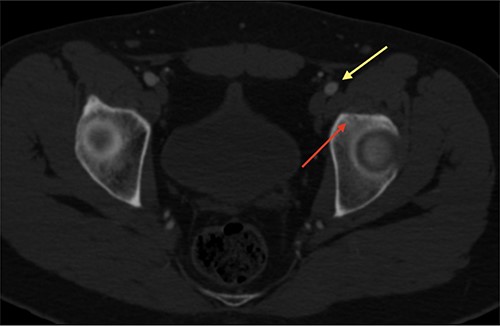

An 18-year-old male with 18 months of left hip pain was referred to an orthopedic surgeon for evaluation. Pain occurred with all hip movements, predominantly at night. Physical examination of the hip showed pain with deep palpation on the groin and positive test for flexion adduction and internal rotation and Patrick test. X-rays were obtained and femoroacetabular impingement (FAI) with labral tear was suspected (Fig. 1). A magnetic resonance imaging (MRI) showed no hip labrum or chondral defect. Measurements for bone deformities of cam and pincer were normal. Physical therapy and nonsteroidal anti-inflammatory drugs were prescribed with some pain relief especially at night. After no improvement of symptoms he was evaluated by a hip surgeon. Intra-articular hip injection with steroids was given and pain disappeared but nocturnal pain recurred after 24 h. Due to the clinical setting and poor response to pain management, an OO was suspected and (CT) was ordered where a 6 mm sclerotic bone tumor with a nidus in the anterior rim of the left acetabulum was identified and corresponded with the pain localization (Fig. 2).

CT scan of the left hip showing a 6-mm extra-articular OO on the anterior rim of the acetabulum (yellow arrow).